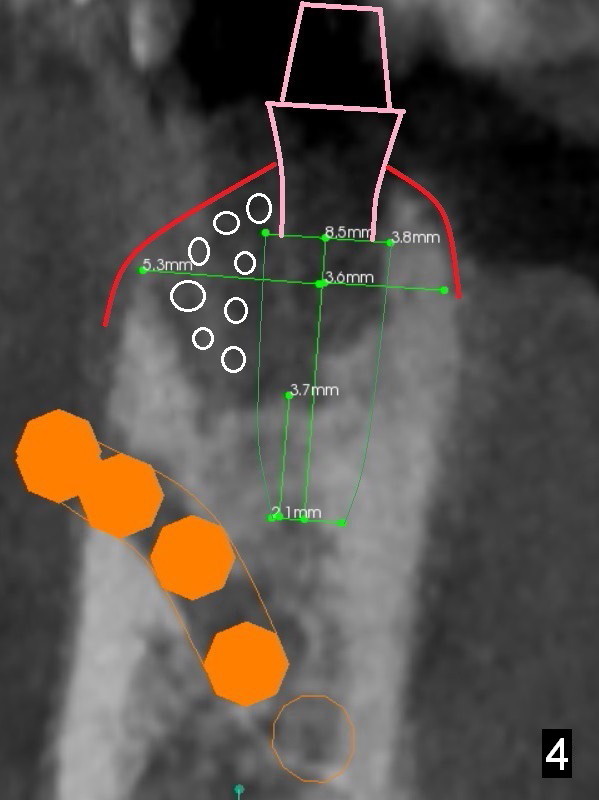

A 71-year-old man loses the implant at #29 five years post placement (Fig.1; 3 years post panoramic X-ray). The attached gingiva is nonexistent at #29 and 30. Gingival graft is necessary. The implant at #29 is placed as mesial (Fig.2) and lingual (Fig.5) as possible. If the implant at #30 is salvageable, place bone graft around the exposed implant threads (Fig.4,5 white circles). Cut a piece of 6-month collagen membrane, use a 4 mm tissue punch to punch 2 holes in the membrane (Fig.6 red circles) and cut open the hole for #30 lingually. Cover the membrane over the graft (Fig.5 red line), followed by PRF membranes (draw 5-6 tubes of blood).

Since the buccal plate is lower at #30 (Fig.7), place a new implant as lingual as possible if the existing one is deemed nonsalvageable. To distribute occlusal load and increase longevity of the implants at #29 and 30, an implant should be placed at the same time or later (Fig.2,8). Approximately 1.5 years later (after #19 implant), the patient returns with intention to restore missing teeth #29-31. The implant at #30 has been lost. CT will be taken for guided surgery. Also take photos to show whether there is lack of the keratinized gingiva at the ridge, as it is related to guided surgery. If the tough gingiva is missing, incision instead of tissue punch should be done prior to osteotomy.